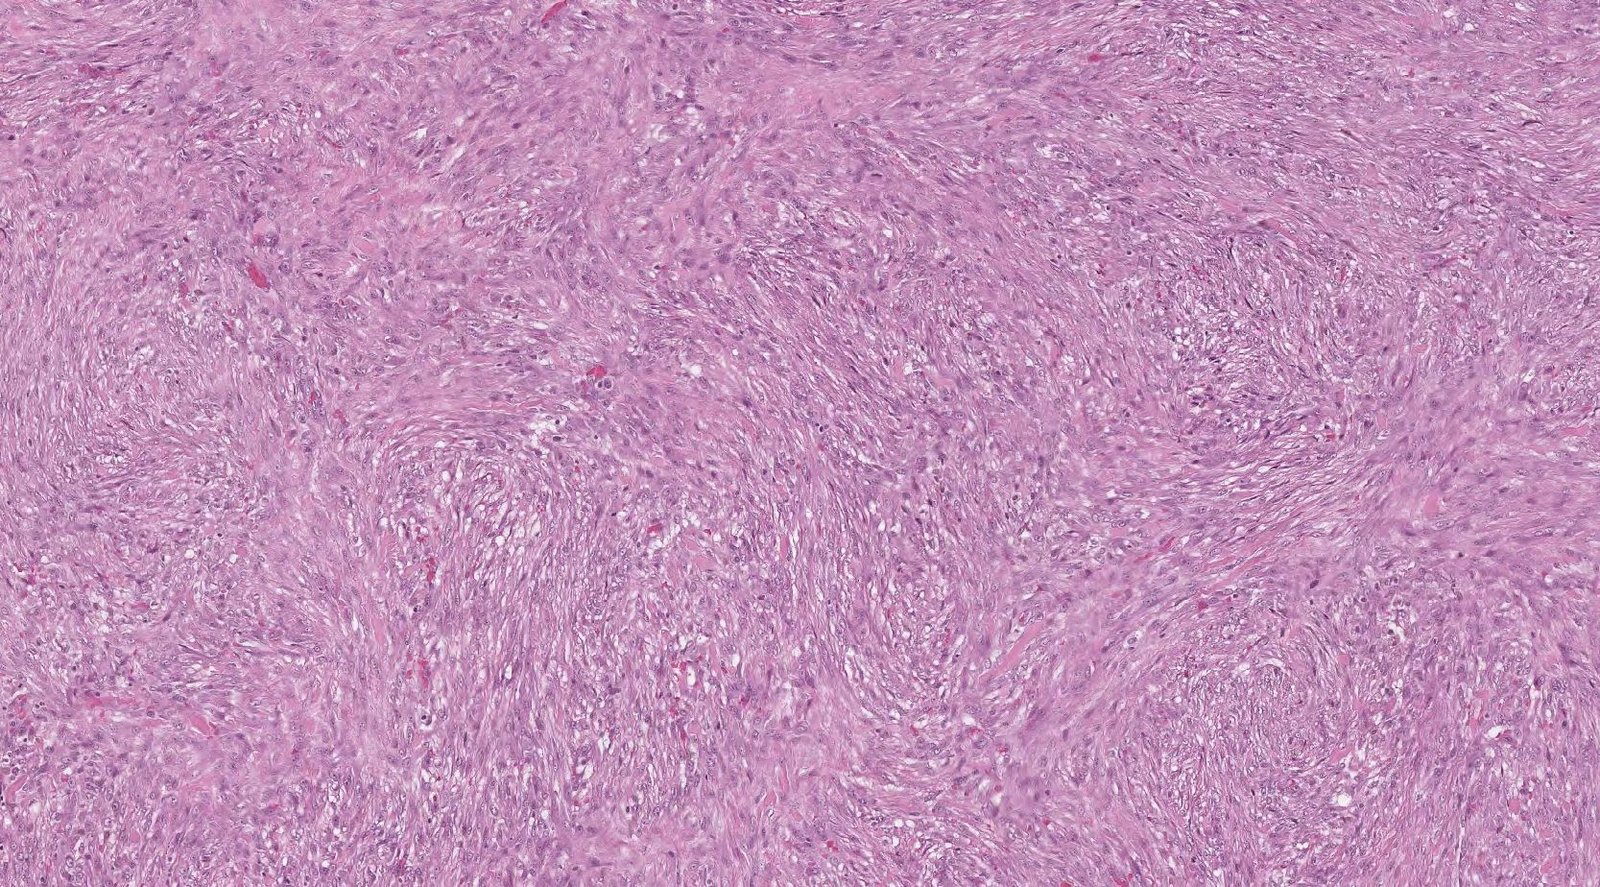

Case: WristMass

Final Diagnosis: